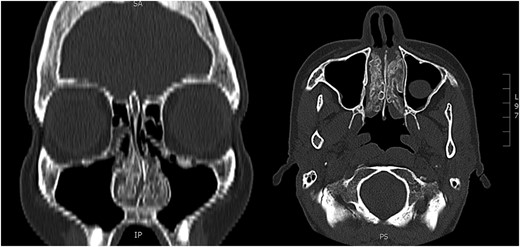

A biopsy of the inferior turbinate undertaken elsewhere reportedly showed benign cartilage and reactive looking bone. Computerized tomography (CT) of paranasal sinuses described hypertrophic bony change confined to the inferior and middle turbinates bilaterally and a deviated septum to the left. The radiological features were suggestive of a benign enchondroma involving both inferior turbinates (Fig. 1). The patient underwent endoscopic inferior turbinectomies in order to achieve a patent nasal airway. A combination of curetting and fracturing of the abnormal bone was required to achieve this. Throughout the dissection, bony adhesions were noted to the septum that needed to be divided to aid in removing the inferior turbinate. An absorbable dressing was placed with the patient instructed to perform regular saline nasal douching during the postoperative period.

Preoperative CT. Paranasal sinuses (coronal and axial) showing bilateral inferior turbinate tumour.